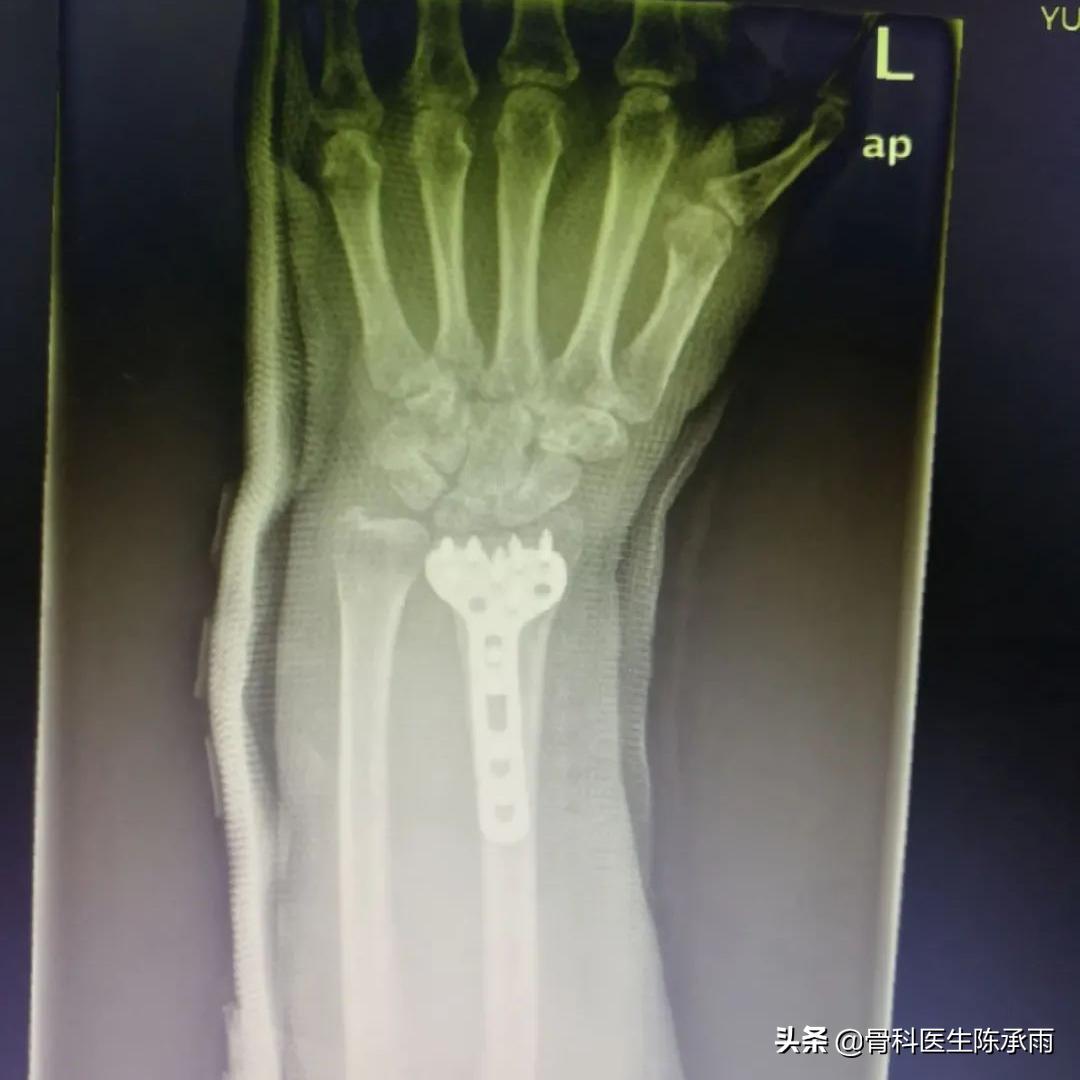

制定手术方案,术中见骨折愈合稳定,骨质疏松严重,远尺桡关节脱位固定,腕关节旋转受限。

原有骨折关系已不能找到,软组织粘连严重,骨折较疏松,尽量达到功能复位。

术后患者恢复良好,患者满意,终于露出久违的笑容。